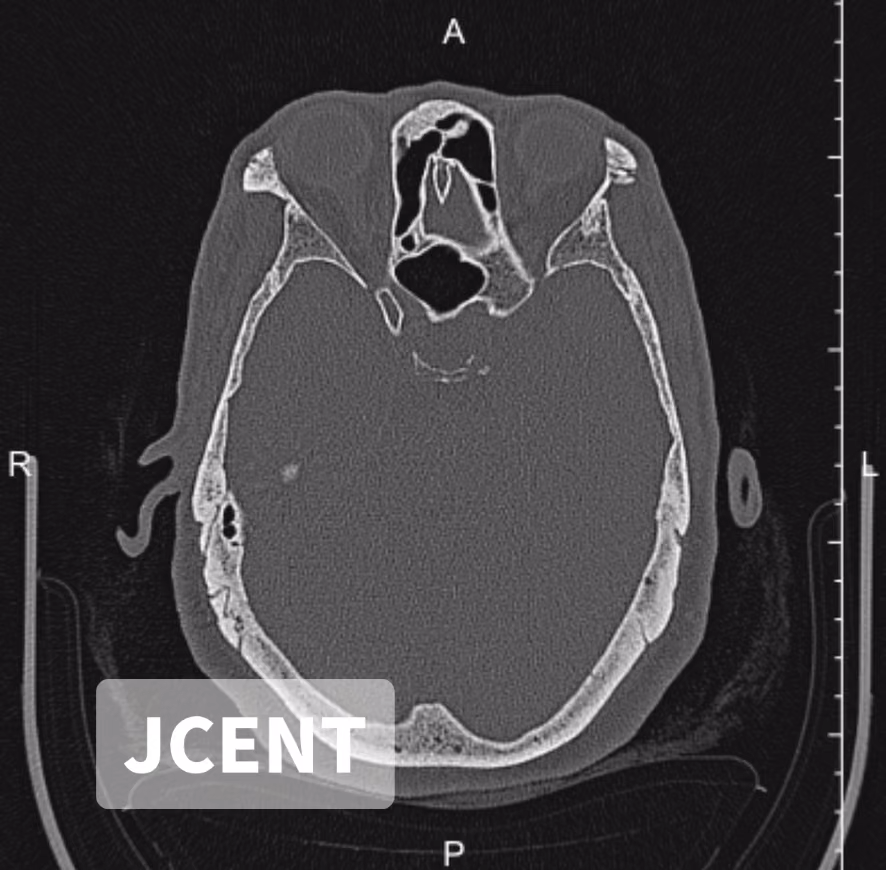

患者女性,59岁,自幼右耳听力差,左耳听力下降20余年,左耳佩戴助听器6年,无耳痛、耳溢、耳鸣、头晕病史,助听器辅助交流不好来就诊。耳内镜检查:双侧外耳道通畅,未见异常分泌物,鼓膜标志清;声导抗:双耳A型。行纯音测听、颞骨CT如下: